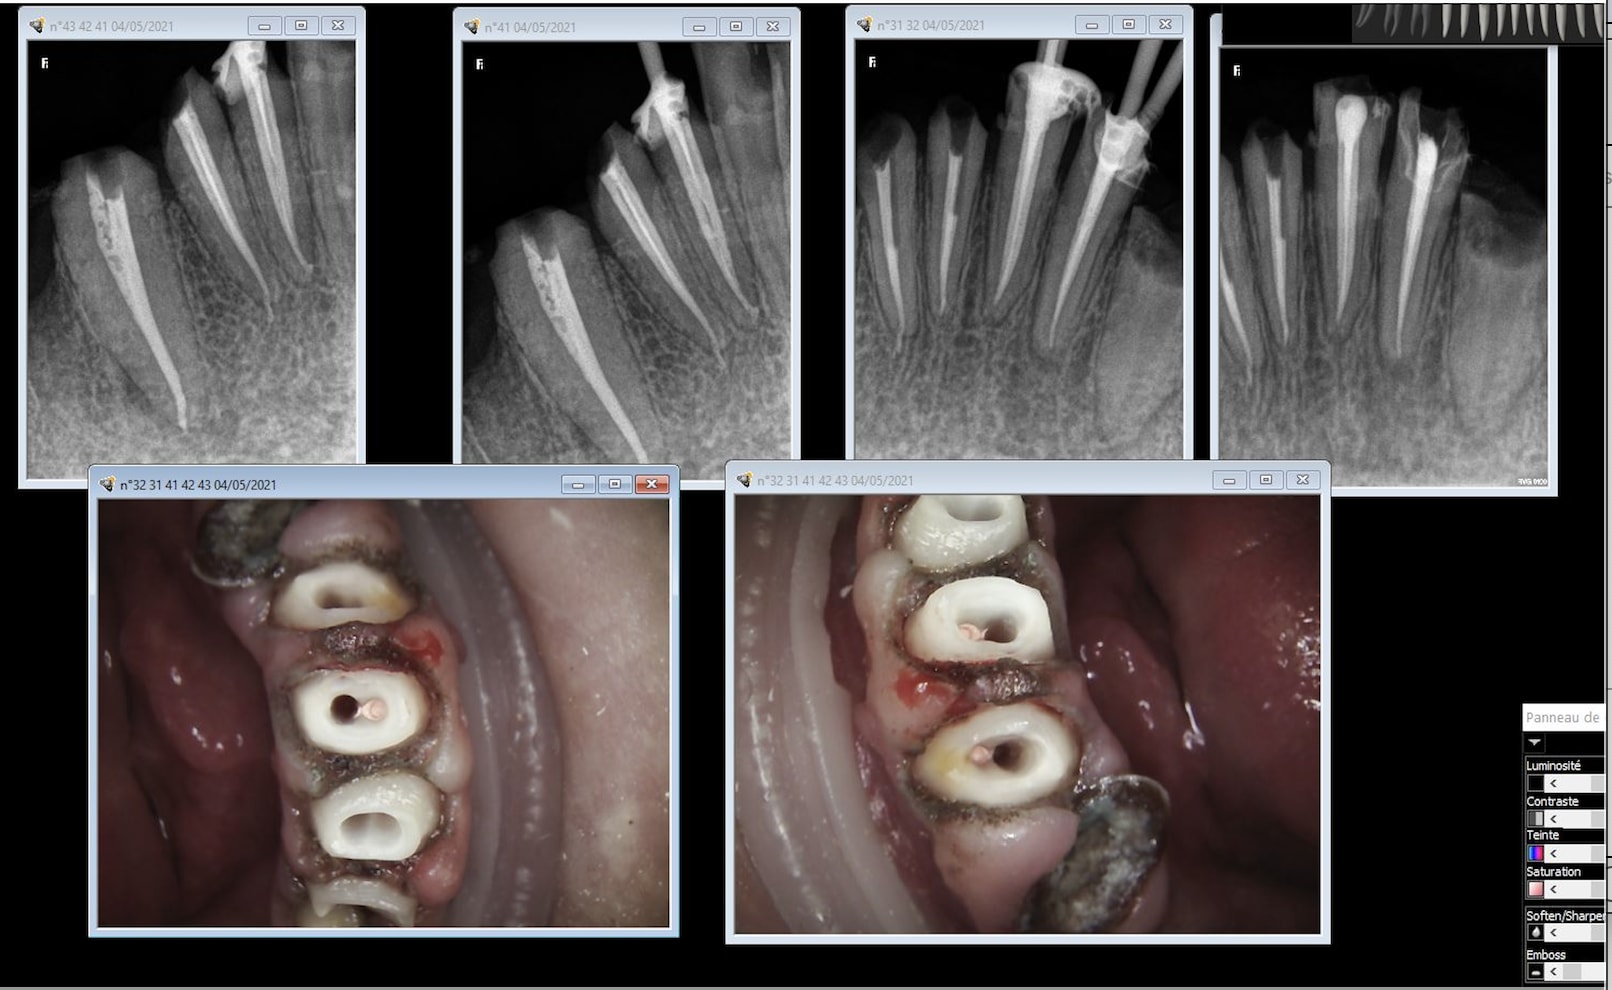

Ab90ka072yua2zqtvwj2dncrm4sj - Eugenol

Jnulth0f9xux31tyok12gyfmt9tx - Eugenol

B7lj33ef6uayyu5ws6kntl9s62na - Eugenol

Capture d  cran 2015 03 12 12.28 - Eugenol

chicot29

23/10/2025 à 22h53

Allez avec un crampon de digue sinon ça fait désordre. -)

26ff2915urgkdt7m9fauq4q8oo83 - Eugenol

23/10/2025 à 23h04

Au départ tu fais tes endos sans digue, puis avec digue en clampant la dent que tu soignes puis tu fais des RCPE et tu ne clampes plus la dent que tu soignes.

U6y97bnl90wb2y37sgb8o3653erq - Eugenol

23/10/2025 à 23h05

Gabzou

23/10/2025 à 23h09

Ben oui facile, regarde tu les a faites magnifiquement.

Bon, chapeau pour la 2ème qui a une séparation des canaux assez basse qui a du être assez pénible à préparer et la négociation de la courbure de la 4ème. Les autres ont 2 canaux mais l'accès semblait relativement aisé et leur naissance assez haute pour qu'on ne puisse pas vraiment les rater.

Et très sérieusement et je pose la question car je me la pose vraiment, pour chacune de ces dents, est-ce que tu considères qu'elles ont été difficiles à traiter?

J'entends par là avec un risque d'échec (casse, oubli de canal, obturation incomplète, ...) élevé qu'un praticien lambda consciencieux qui aurait pris le temps nécessaire n'aurait pas sur gérer, et que toi tu as su gérer uniquement grâce à ton expérience (et tes formations peut être?) ?

23/10/2025 à 23h16

Aucune, mais ça serait plus simple si à la base on t'apprenais à les faire correctement. -)